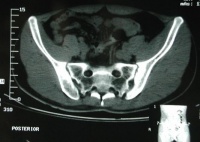

以骶髂关节炎最为突出。骶髂关节出现x线征象时往往已较迟,几乎完全是双侧性。最初出现的是关节附近

退变性骶髂关节炎

有斑片状骨质疏松区,特别是骶髂关节的中下段最为明显。接着便出现了骨腐蚀与软骨下骨皮质硬化。在骶髂关节的中下段,髂骨面覆盖着薄层软骨,因此该处首先出现骨骼变化,且比较明显。在骶髂关节的上1/3处,有坚强的韧带连接着骨面,也可以有类似的X线征象。

软骨下骨侵蚀的X线表现为关节间隙的假性增宽。接下去便是纤维化、钙化、骨桥形成与骨化。一般说来,软骨下骨皮质硬化比骨腐蚀明显些,最终骶髂关节完全强直,通常需数年之久。